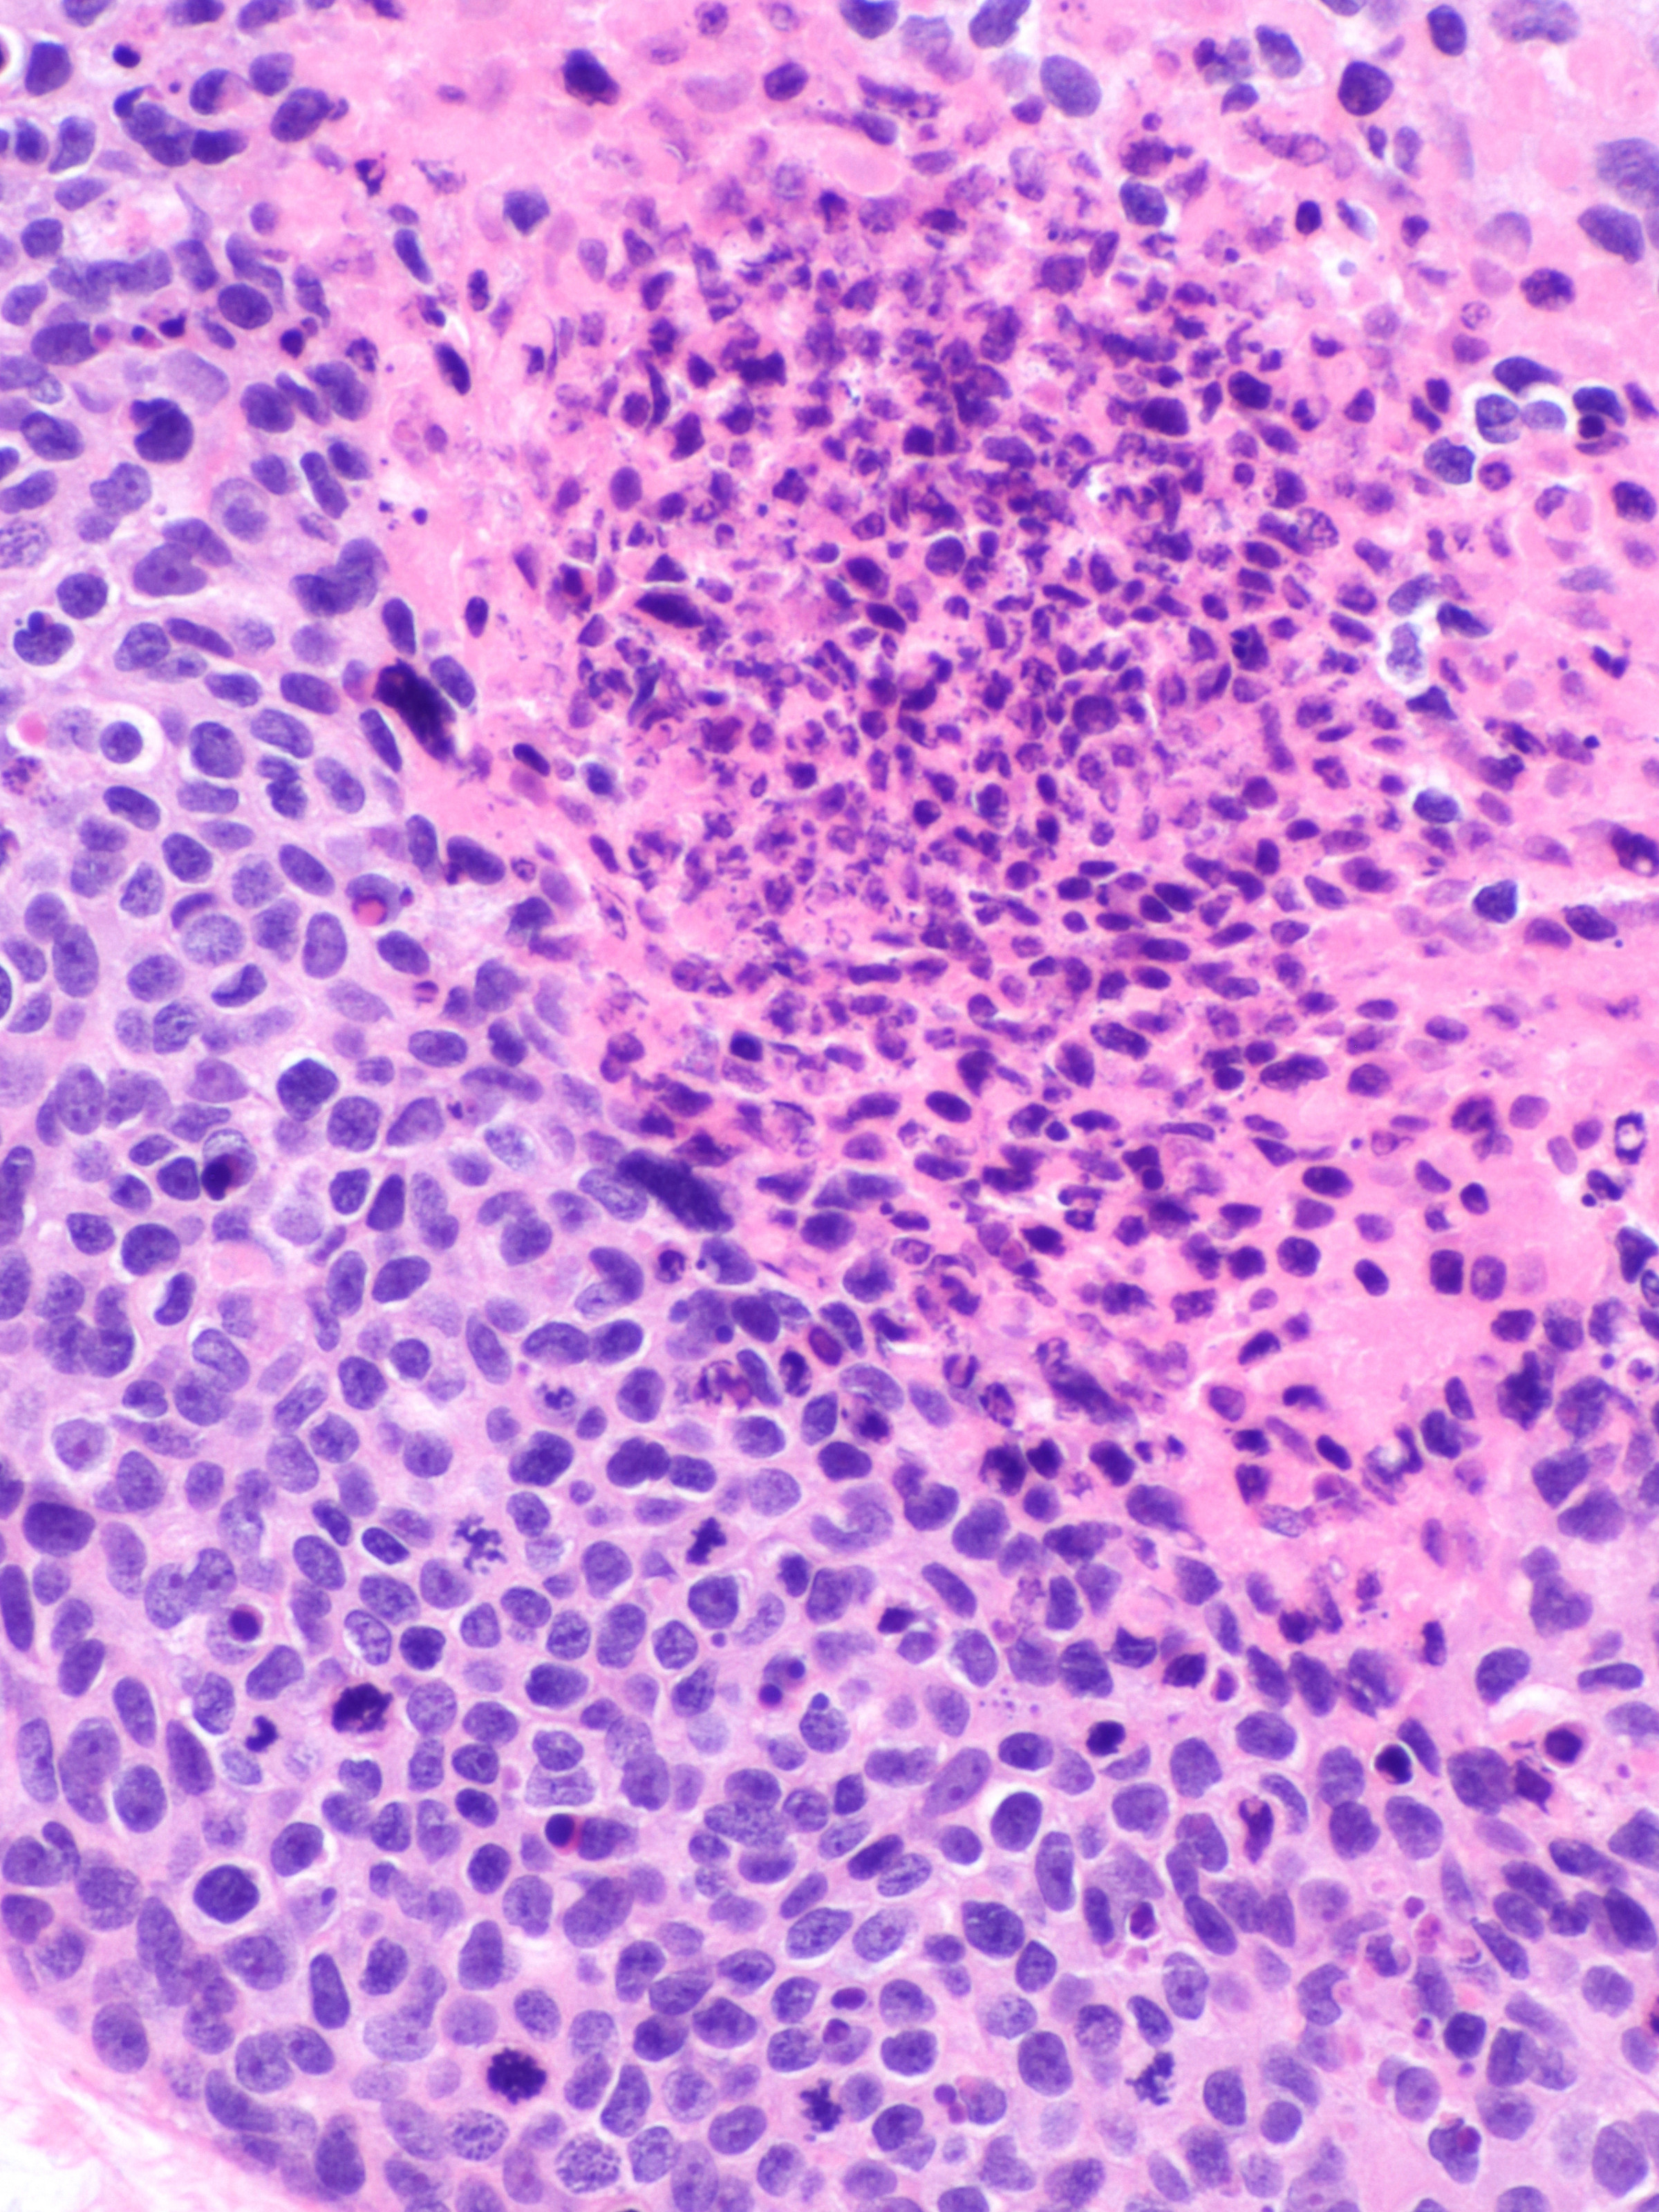

PA:

Multipele velden van basaloïde polygonale tumorcellen cellen met plaatselijk

ductale differentiatie, buis structuren met cuboïd epitheel. Uitgesproken cytologische

atypie, mitosefiguren. Soms ook squameuze differentiatie en dyskeratotische

cellen. Immunohistochemie: de ductale structuren kleuren aan met CEA (carcinoembryonic

antigen) en EMA (epithelial membrane antigen). De tumoren zijn meestal positief

voor CD117 (KIT), cytokeratin 19, c-KIT, en BerEP4. De prognose is slecht als

er invasie is van lymfbanen en vaten, meer dan 14 mitoses per high-power veld

en bij een tumordiepte > 7 mm.

| histologie

porocarcinoom |

histologie

PA-foto's: Michael Bonert (Nephron) - Wikimedia - Creative Commons License

3.0).